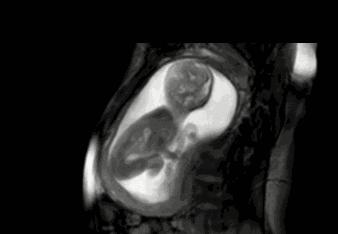

在孕妈的一整个孕期都有很多需要注意的地方,尤其是随着胎儿的逐渐长大,不可能每天都去医院检查胎宝是否健康,此时数胎动就成为孕妈观察胎宝健康状况的一个重要举动。只是,作为新手孕妈,你真的会数胎动吗?

胎儿在孕妈肚子里的动作都是不一定的,有可能用脚踢一下,有可能用手锤一下,小雨就是将这每一个动作都计算为一次胎动。其实真正的一次胎动,是胎宝的一个连续的动作。一般这个计算时长在一分钟左右,或者在隔了有五分钟以上,再有胎动的时候记为第二次胎动。

有些孕妈比较心急,从20周,甚至16周就开始数胎动,其实这个月份数下来并不是很准。因为在这个阶段,孩子的胎动并不是很明显,频率也比较低。一般建议是在28周,也就是胎儿七个月的时候,孕妈开始数胎动。这个时间段的胎动最为活跃,孕妈也最需要注意胎儿的健康。

胎儿的胎动和孕妇的体位也有着密切的关系,数胎动最好的姿势是,左卧。因为在站立、右卧或者平躺的时候,胎儿的胎动次数相对较少。